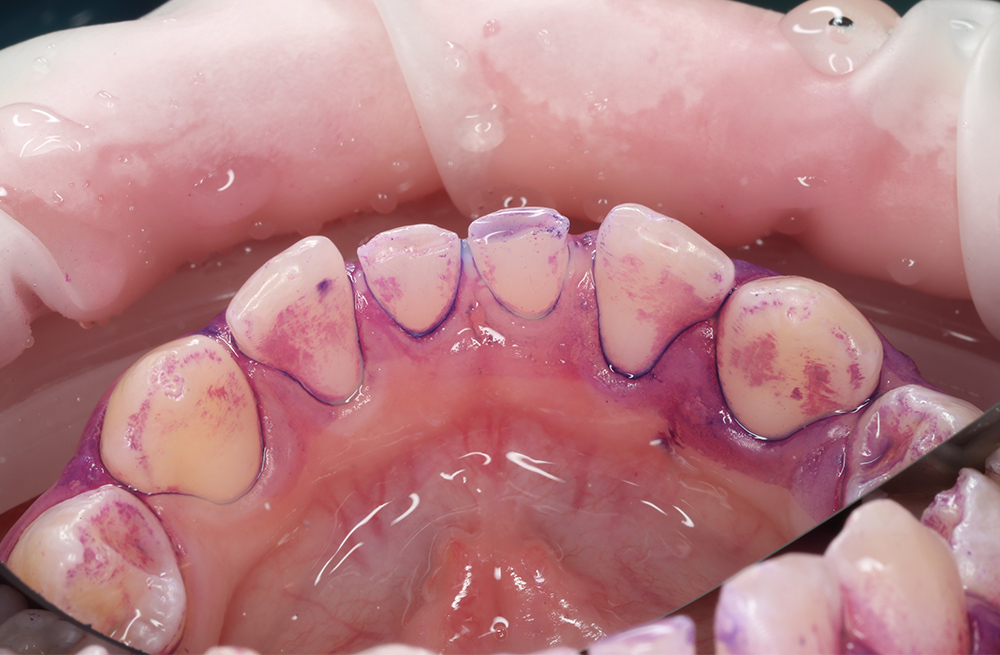

Удаление мягкого и пигментированного налёта у подростка с использованием Air-flow